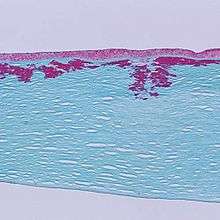

| Reis-Bücklers corneal dystrophy. Reticular opacity in the superficial cornea | |

Patients with Reis-Bücklers dystrophy develop a reticular pattern of cloudiness in the cornea. This cloudiness, or opacity, usually appears in both eyes (bilaterally) in the upper cornea by 4 or 5 years of age. The opacity elevates the corneal epithelium, eventually leading to corneal erosions that prompt attacks of ocular hyperemia, pain, and photophobia. These recurrent painful corneal epithelial erosions often begin as early as 1 year of age.[3]

With time, the corneal changes progress into opacities in Bowman's membrane, which gradually becomes more irregular and more dense.[3] Significant vision loss may occur.[4] However, vascularization of the cornea is not present.[4]